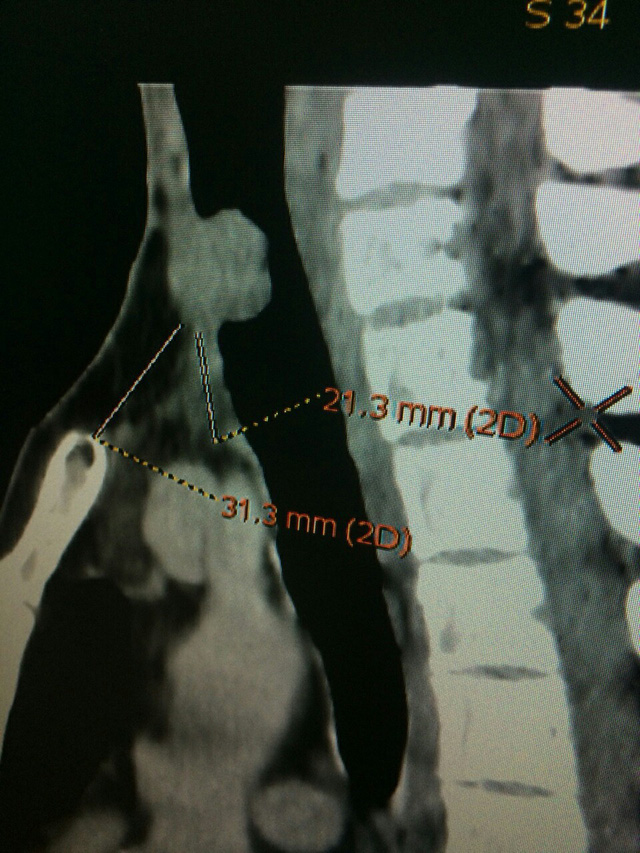

Bệnh nhân nhập viện trong tình trạng ho ra máu. Qua thăm khám lâm sàng và xét nghiệm, phát hiện ung thư tuyến giáp đã tái phát, di căn vào lòng khí quản, gây hẹp lòng khí quản khiến bệnh nhân ho ra máu, có nguy cơ vỡ u, gây suy hô hấp dẫn đến tử vong bất cứ lúc nào.

| Phim chụp X - quang vùng cổ của bệnh nhân |

Ngày 20/4, bệnh nhân đã được phẫu thuật. Sau khi được gây mê bằng mask thanh quản, bệnh nhân được phẫu thuật cắt đoạn 4 sụn khí quản kích thước 4cm (bướu chiếm 3cm) mang khối tái phát với rìa an toàn 5mm, sau đó cắt các cơ trên móng để giải phóng đoạn trên khí quản và được nối tận - tận hai đầu khí quản vào lại với nhau.